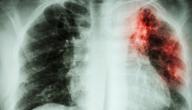

- التصوير بالأشعَّة السينيَّة: قد تُبيِّن هذه الصورة النسيج الندبي في الرئتين، إذ يعطي هذا الفحص مجموعة من الصور لصدر المريض، وفي بعض الحالات تكون هذه الصور طبيعيَّة، ممَّا يعني الحاجة إلى المزيد من الفحوصات لتفسير سبب ضيق التنفُّس، وقد يكون هذا الفحص مفيداً لمراقبة المرض والتحكُّم في العلاج.

- التصوير المقطعي المحوسب: تساعد الصور ذات الدقَّة العالية الناتجة عن التصوير المقطعي المحوسب (بالإنجليزية: Computed tomography scan) بشكل خاصٍّ على تحديد مدى الضرر والتلف الحاصل في الرئتين الناجم عن التليُّف الرئوي، إذ إنَّ بعض أنواع التليُّف الرئوي لها أنماط مميَّزة، ويُستخدم في هذا التصوير جهاز الحاسوب للدمج بين العديد من صور الأشعَّة السينيَّة المأخوذة من زوايا مختلفة لإنتاج صورٍ مقطعيَّة لأعضاء الجسم الداخليَّة.